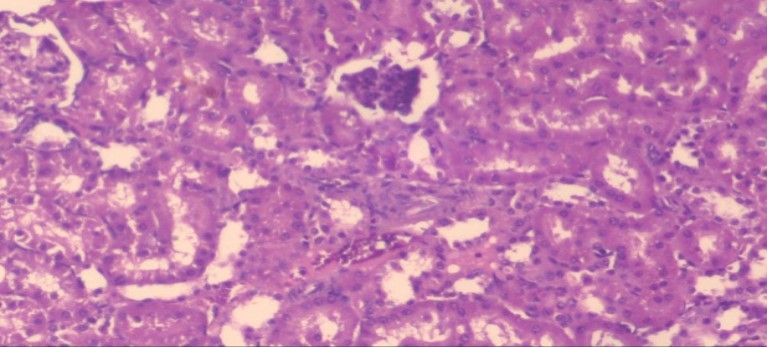

The histological examination of the kidney of the control rats fed on a standard diet showing normal rounded capsules with normal Bowman's glomeruli, round proximal tubules and elongated distal tubules with high cuboidal cells figure 1. The rats fed (HFD) showed fatty degeneration of the tubules with eosinophilic material deposition, glomerular atrophy with wide urinary space and distal tubules with extrusion of nuclei into lumen figure 2. By comparison kidneys of rats which were treated by fennel after being obese and the control rats observed partial improvement in both Bowman's capsules and proximal tubules. Note the distal tubules show less focal fatty infiltration figure 3.While examination of rats kidney that were treated by ator after obesity showed improvement in Bowman's capsules with normal glomerular and partial improvement in proximal tubules and distal tubules, figure 4. Kidney of rats that were treated by fennel and ator after obesity and the control rats showed high improvement in the tissues with normal glomerular and that Most of Bowman's capsules and renal tubules, restoring their normal appearance figure 5.

Figure 5.Photomicrograph of kidney section of treated rat with both fennel herb and Ator drug showing highly improved tissue with normal glomerular. Note, most Bowman's capsules and renal tubules, restoring their normal appearance (star). (H&E) (40X).